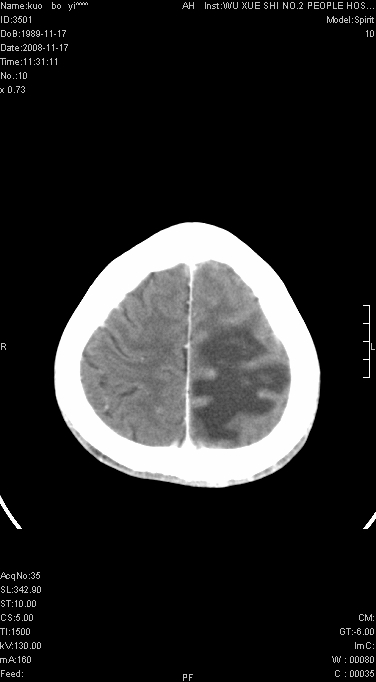

增强已传.年龄19岁.请会诊

增强后水肿中心高密度灶有明显强化,强化不均匀,呈雪花状或絮状,且强化明显,若为肿瘤,应该出现形态较规则的瘤体影,强也有例外如胶质瘤就可以形态不规则.但胶质瘤明显强化者多为恶性间变性,与病史及相关表现太不相符.因此本例多考虑为炎症引起.

本例与重庆中华放射学年会读片大赛上第12个病例(由山东医影研究所柳澄教授提供)有异曲同工之妙(影像表现几乎相同).那个病例我的第一选择是炎症,其次是血管畸形,最后选项择的占位.但得到的答案是ms,新发的ms灶可见明显强化,但这么大的病灶着实没有想到,可能本例就影像表现来说也不能排除ms可能

患者年龄才19岁,病史很短,也较符合炎症等短程病变.

左顶叶较大范围水肿区,内见明显强化的片状 棉絮状组织,但占位效应不明显。多考虑:脑炎!

首先考虑脑胶质瘤。有明显的左顶叶脑白质水肿,病变轻度占位效应,花环样强化,脑炎——影像不支持!

在北京天坛医院治疗考虑寄生虫感.明显好转